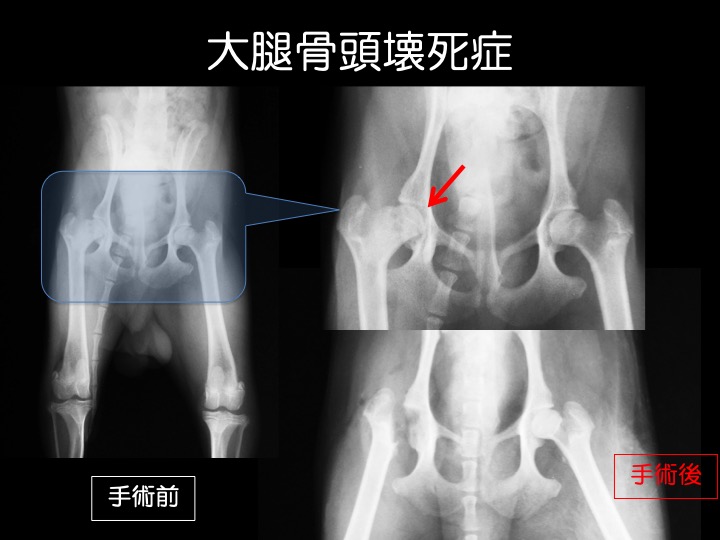

成長期の小型犬に多い疾患です。

・股関節を形成する大腿骨頭(太ももの骨と骨盤との連結部)が壊死を起こし、関節炎や骨折を起こす、原因不明の病気です。人にも同じ病気があり、その発見者の名前から「レッグ・カルベ・ペルテス病」とも呼ばれます。

・足を挙げたり、かばうように歩く、痛がるなどの症状がみられ、ほとんどが進行性に悪くなるため、内科治療で改善がない場合、「大腿骨頭切除術」という手術が行われます。